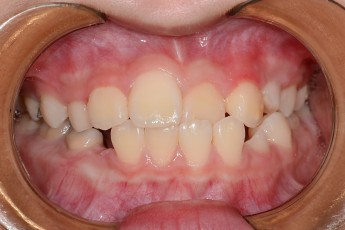

BEFORE & AFTER

- 덧니교정